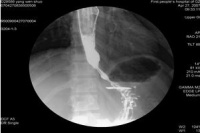

1.钡餐检查 钡餐常难以通过贲门部而潴留于食管下端,并显示为1~3cm长的、

对称的、粘膜纹政党的漏斗形狭窄,其上段食管呈现不同程度的扩张、处长与弯曲,无蠕动波。如予热饮,舌下含服硝酸甘油片或吸入亚硝酸异戊酯,每见食管贲门弛缓;如予冷饮,则使贲门更难以松弛。潴留的食物残渣可在钡餐造影时呈现充盈缺损,故检查前应作食管引流与灌洗。